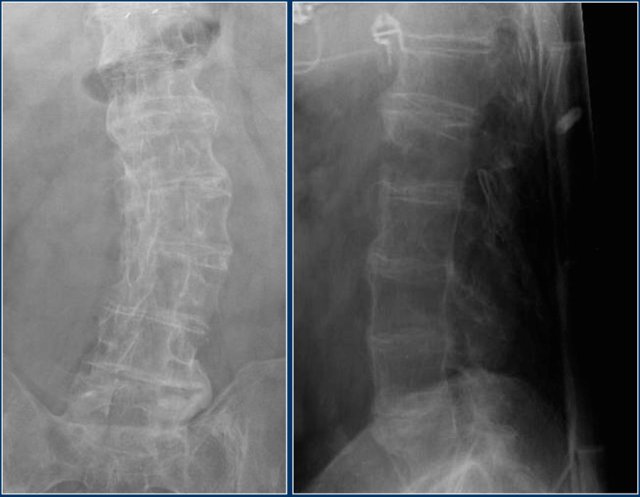

The images show two cases of osteochondrosis.

On the right with kyphosis.